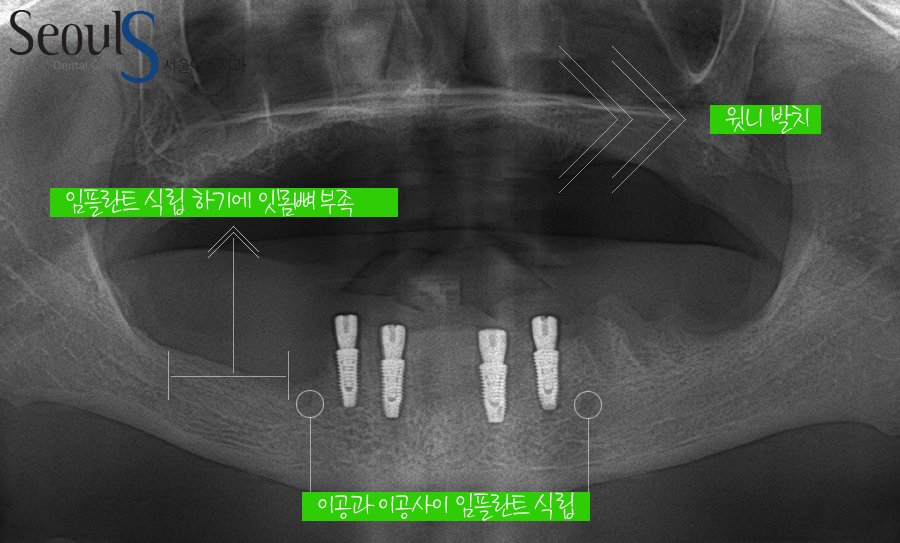

내원 당시 X-ray 사진입니다

윗니는 잇몸 염증으로 잇몸뼈가 소실된 상태로 치아가 흔들리는 상황입니다

안타깝지만 치아를 살릴 수 없는 상태!

치주염으로 다수의 치아가 한꺼번에 흔들리는 상황으로

아래 치아도 잇몸뼈가 소실된 모습으로 대부분의 치아를 살릴 수 없는 상태입니다

아랫니를 보시면

턱부터 신경관이 나오는 부분(이공)까지는 임플란트를 식립할 때 신경을 건드리면 안되니…조심스러운데요

아랫니가 빠지고 오랜 시간 동안 방치되어 잇몸뼈는 흡수되었고

아래 어금니에 임플란트를 식립하려면

많은 잇몸뼈 이식이 필요한 상황입니다

아래 어금니에 잇몸뼈 이식과 함께 임플란트를 식립하는 것은 가능하지만

비용과 시간, 환자분께서 고생하시는 것을 생각할 때

아랫니는 뼈이식 없이 이공과 이공 사이~ 신경관이 없는 부분에 임플란트를 식립 할 예정입니다

신경관을 피해 임플란트 4개를 식립했습니다